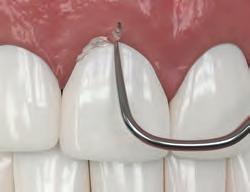

2. Give firm air/water spray to remove residual coagulum and to test for profound hemostasis. If bleeding continues, repeat.

3. After complete hemostasis has been attained, excellent retraction is achieved using Ultrapak™ knitted cord placed with the Ultrapak™ packer.

1. Place Ultrapak™ knitted cord soaked in hemostatic solution using a cord size that appears slightly too large to ensure cord retention. The thin Ultrapak™ Packer quickly slips cord into position. The knitted cord’s unique design (interlocking loops) facilitates easy packing and locks it into place.

PREPARATION

2. Extend margin subgingivally by cutting partway into knitted cord, which won’t entangle in diamond bur. Remove remnant of cord with an explorer or other instrument. Bleeding is minimal if at all. A small portion of uncut tooth above gingival attachment is preserved to record in impression. If additional retraction is required, repack with appropriately sized cord. Rinse, air dry, and make impression.